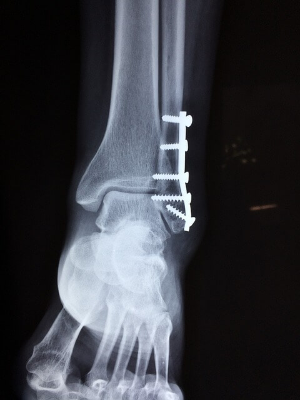

- 고정 – 핀 및/또는 금속판을 사용한 고정은 골절을 치료하는 데 사용할 수 있습니다. 이것은 골절이 심하게 변위되어 의사가 올바르게 치유하기 위해 골절을 재정렬해야 할 수 있는 경우에만 필요합니다.